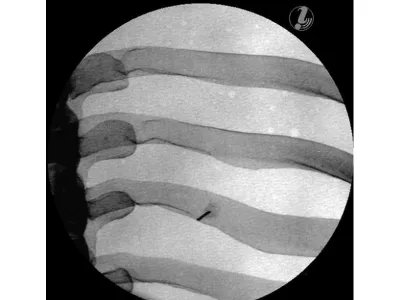

Манекен для инъекций имеет анатомически точную костную структуру (позвонки T3-T8, ребра 3-8) и реалистичную тактильную обратную связь в ходе практики. Кроме того, он выполнен из самовосстанавливающегося материала, который позволяет многократно использовать тренажер.